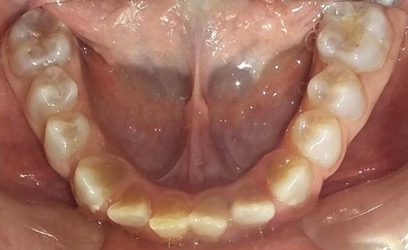

En el último control realizado en el año 2018 (Figura 11) el paciente mantuvo el estado de salud logrado. El análisis cariogénico fue moderado (por su historia pasada de caries y su condición biológica específica) y el gingivoperiodontal bajo. El paciente continúa en atención en la COIN. Fue derivado en varias oportunidades al servicio de Ortodoncia de la Facultad de Odontología de la Universidad de Buenos Aires, pero hasta el momento no encaró ningún tratamiento propuesto.

Cuando la dentición permanente está implicada, los incisivos inferiores son los más comprometidos, presentando en estos casos una coloración intensa propia de la DI (O’Connell, Marini 1999, Majorana, Bardellini et al. 2010, Petersen, Wetzel 1998), como se observa en el paciente. Las piezas permanentes fueron monitoreadas desde su erupción, recibieron protocolos preventivos con barnices fluorados, pastas y enjuagatorios fluorados domiciliarios, conjuntamente con un adecuado control de higiene oral.15